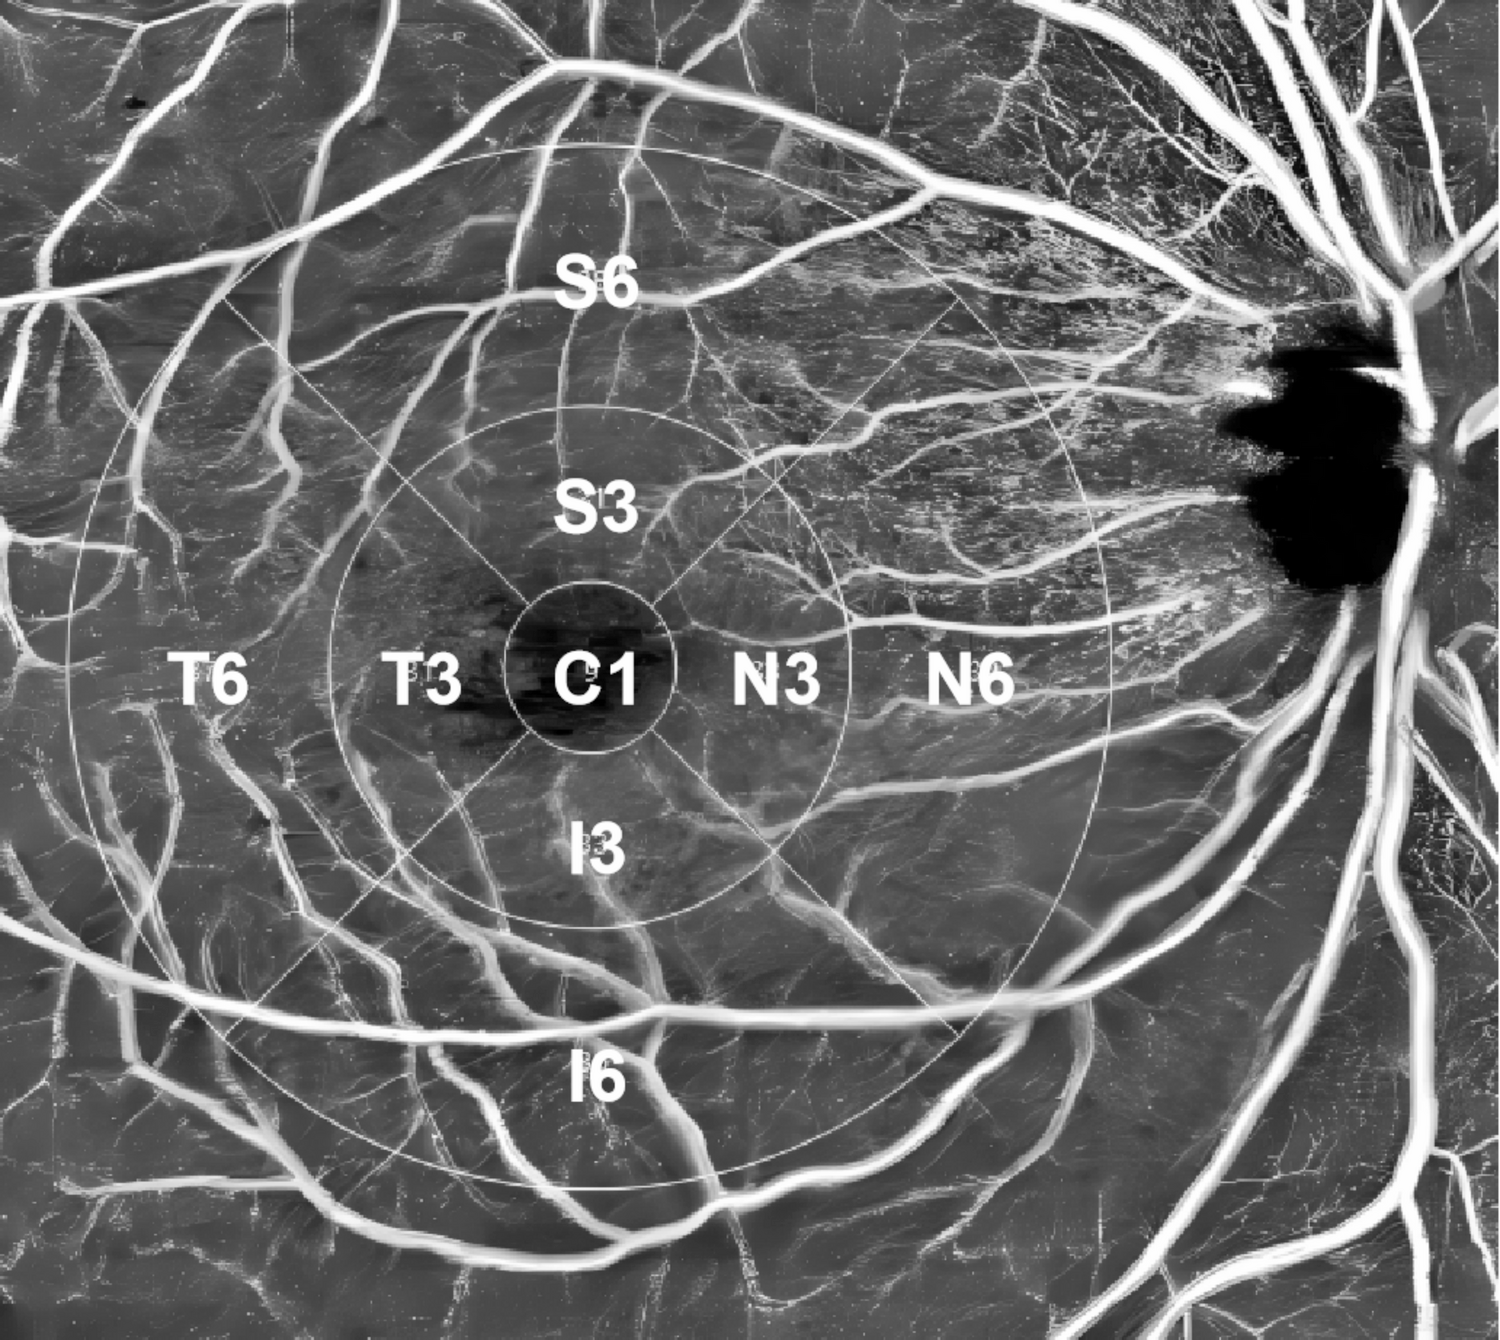

Fig. 2

Illustration of the macular ETDRS grid for retinal and choroidal analysis. The macular region was divided into three concentric rings with diameters of 1 mm, 3 mm, and 6 mm centered on the fovea. Sectors are defined as follows: C1, central fovea (0–1 mm); S3, superior sector within 1–3 mm; S6, superior sector within 3–6 mm; I3, inferior sector within 1–3 mm; I6, inferior sector within 3–6 mm; N3, nasal sector within 1–3 mm; N6, nasal sector within 3–6 mm; T3, temporal sector within 1–3 mm; and T6, temporal sector within 3–6 mm.